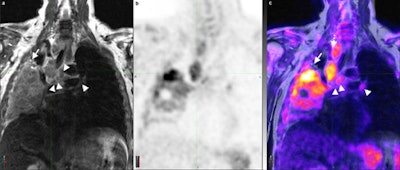

Coronal T2 turbo spin-echo sequence (a) of the chest and corresponding PET and PET/MR fusion (b, c) demonstrates a non-small cell lung cancer tumor occupying a large portion of the right lung with multiple enlarged lymph nodes (arrowheads). The superior soft-tissue contrast resolution of MRI allows for the identification of each separate lymph node and confident distinction of lymph nodes from vascular structures (dotted arrow). Similarly, atelectasis can be distinguished from tumor (arrow) even in the absence of intravenous contrast. All images courtesy of Dr. Andres Kohan.For PET/CT, a standard dose of FDG adjusted for body weight was administered (447.7 ± 70.3 MBq) with imaging starting approximately 60 minutes after injection. PET data were acquired using time-of-flight technology on a standard PET/CT system (Gemini TF PET/CT, Philips Healthcare).